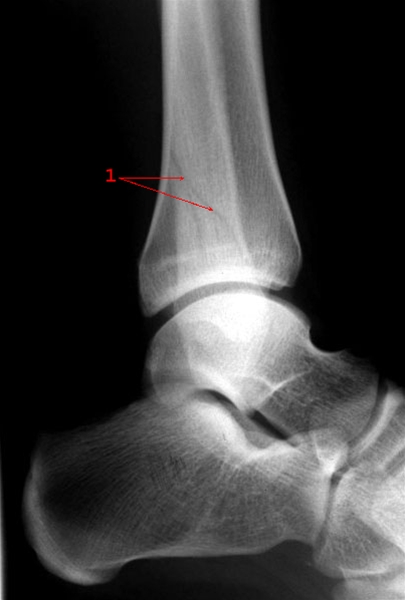

Malleolfraktur, sideoptagelse

Skråfraktur gennem laterale malleol uden fejlstilling (1)